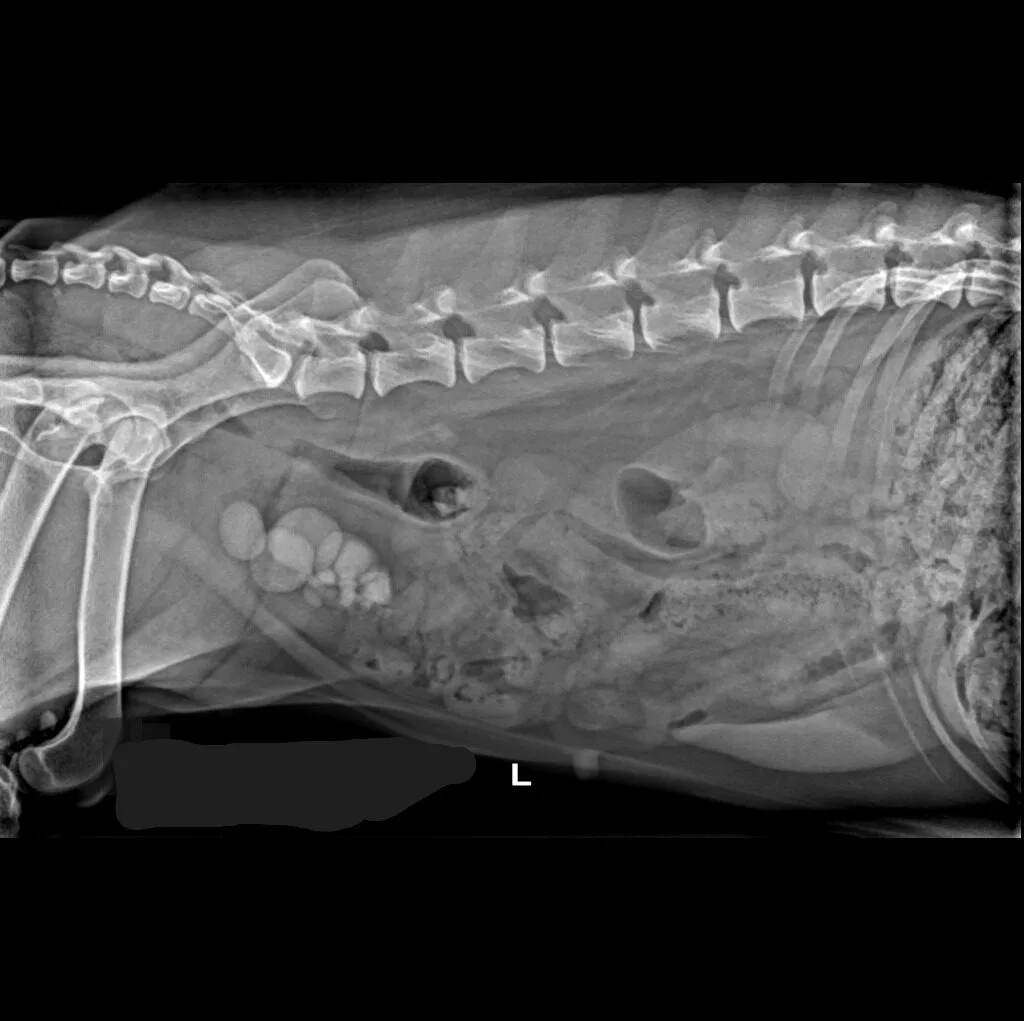

At Grand Ave. Pet Hospital, we utilize digital radiography to diagnose and monitor a wide range of medical conditions in pets. Digital X-rays provide clearer images, faster results, and safer radiation levels, ensuring the best possible care for your furry companion.

Digital radiography offers superior imaging quality and precision compared to traditional X-ray techniques. It allows us to detect hidden health issues early, leading to faster and more effective treatments.

🔹 Cardiac & Respiratory Conditions – Evaluating heart disease and lung disorders

🔹 Abdominal & Gastrointestinal Issues – Detecting obstructions, tumors, or organ abnormalities

🔹 Cancer Screening – Locating tumors and assessing disease progression